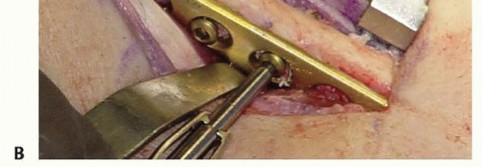

FIG 4 • Ulnar impaction syndrome in a 73-year-old woman after distal radius fracture nonunion and subsequent collapse. She underwent open reduction and internal fixation of the radius fracture as well as ulnar shortening osteotomy to correct the posttraumatic ulnar positive variance. Severe osteopenia prevented stable fixation of the ulnar osteotomy with the standard plate and necessitated a longer eight-hole DCP.